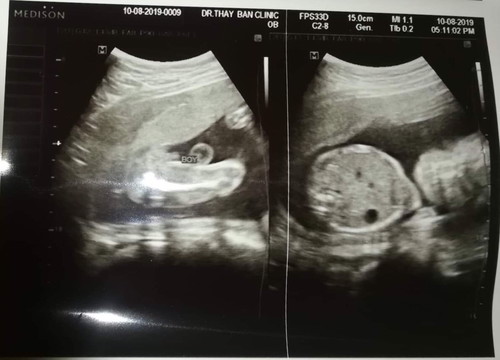

ภาพนี้ซาวด์ตอน 5 เดือน ได้ผู้ชายมีโอกาสเปลี่ยนแปลงบ้างไหมคะ

ตอน3เดือนหมอบอกผู้หญิงไว้ก่อนเพราะเล็กมาก พอ4เดือนน่าจะผู้ชาย พอ5เดือนหมอบอกก็ผู้ชายอยู่ดี ถ้าชัวร์เราจะได้เตรียมของไว้ก่อนค่ะ

บ้านนี้หมอชี้ให้ดูว่าเนี่ยจู๋เนี่ยชัดโด่วเลยชายชัวร์ เราก็เชื่อเลยค่ะ😁